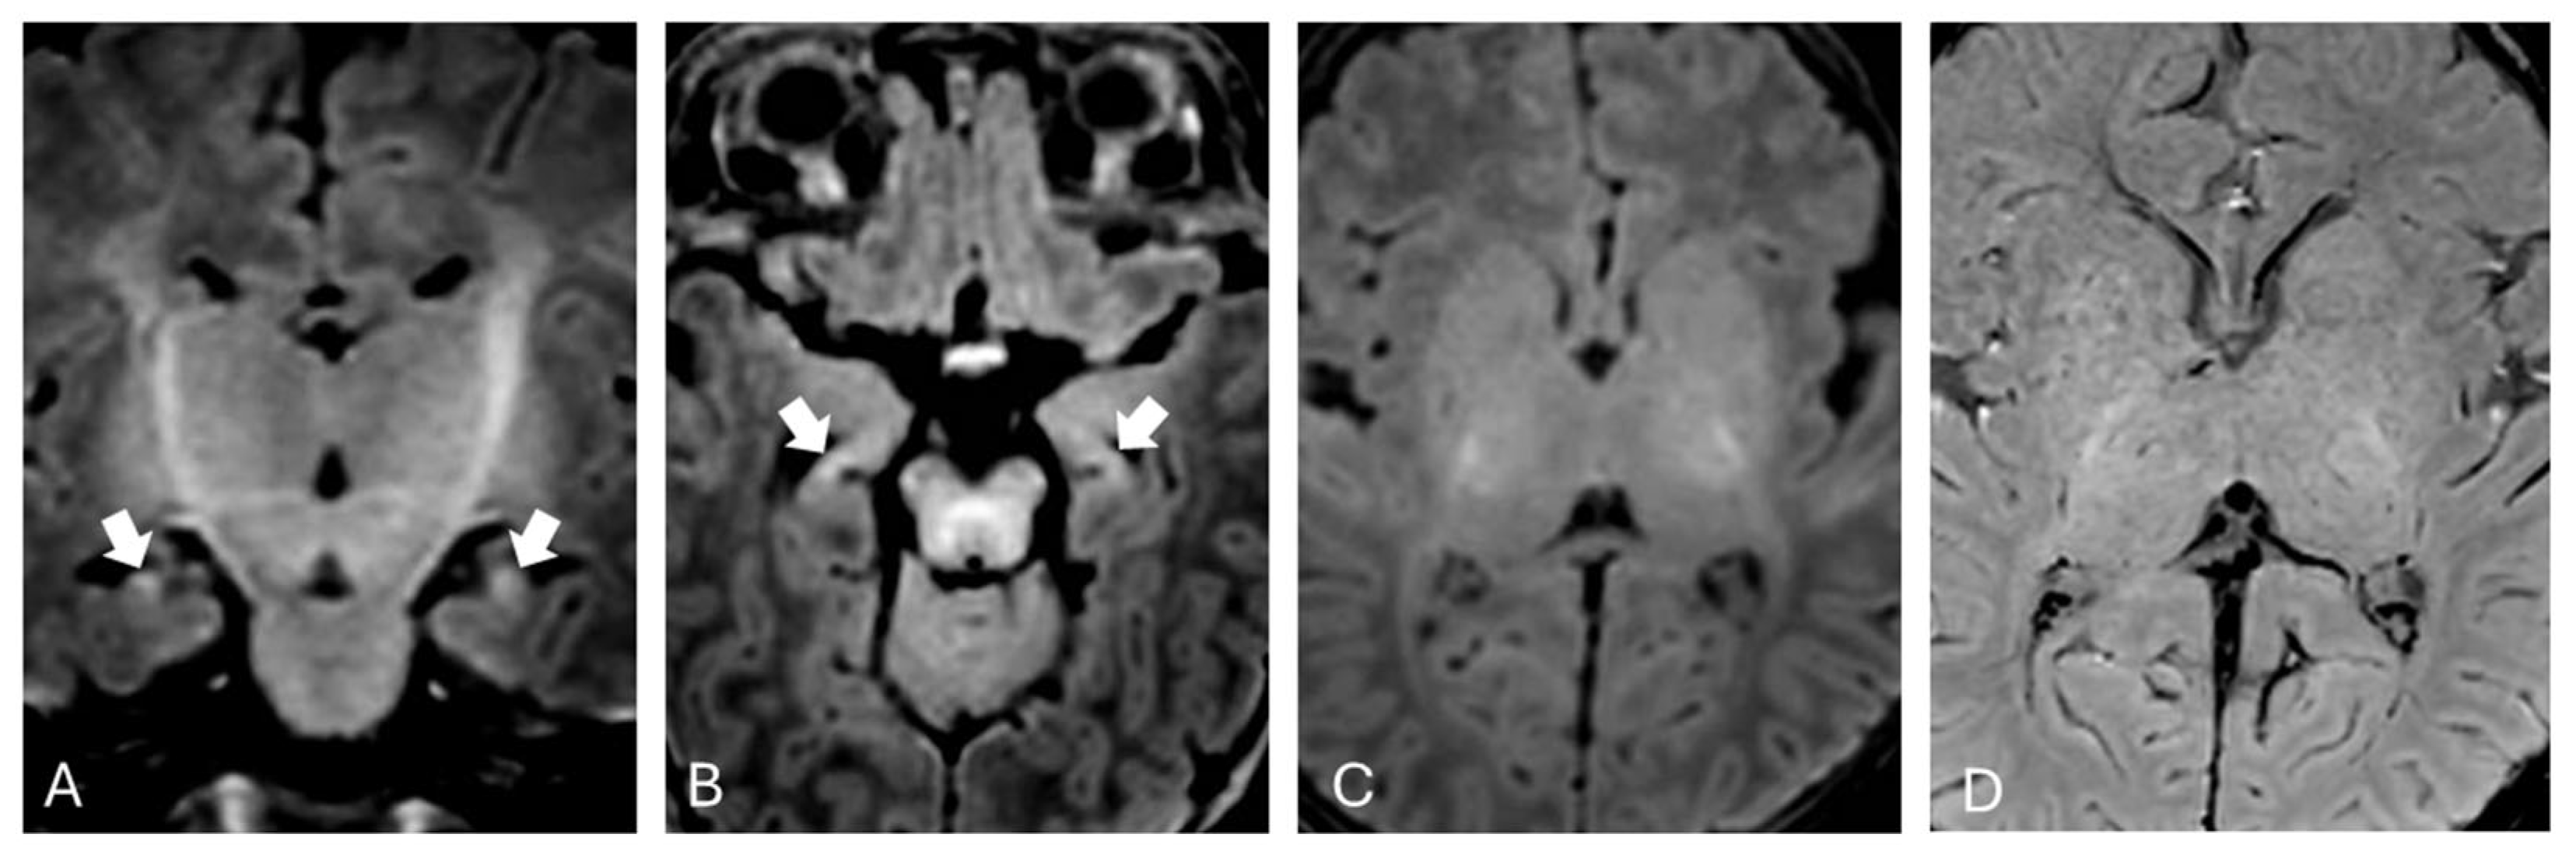

Brain MRI was performed at one month of extrauterine life as expected from existing literature [11] and showed mild T1 hyperintensity in the hippocampi bilaterally (Figure 1).

In our patient, brain MRI performed during the subacute phase revealed hyperintense signal on T1-weighted images within the hippocampi, while T2-weighted images in the same regions appeared normal. No significant alterations were observed in the basal ganglia and subthalamic nuclei on T1-weighted sequences. The absence of obvious alterations in T1-weighted sequences may be attributed to the myelination process, which makes it more difficult to distinguish pathological changes from the expected T1 hyperintensity in these regions during normal developmental processes at this age [19]. This is particularly true when using high-field imaging, which provides a better signal-to-noise ratio. Alternatively, this could be related to the onset of the “blind window” described by Gburek-Augustat et al. [18], which is typically observed around two months of life, during which no alterations are detectable on MRI.

Figure 1. Brain MRI performed during the subacute phase. Hyperintensity in the hippocampi on coronal (A) and axial (B) T1-weighted images (arrows, A,B). No evident changes were observed in the nucleo-capsular region, either in axial T1-weighted images (C) or in susceptibility-weighted images (D).